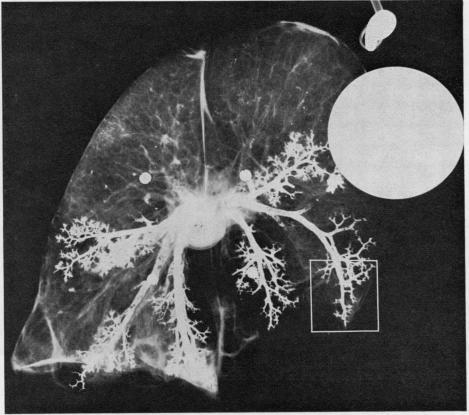

Tantalum bronchography was performed on 22 left lungs obtained at necropsy. Seven were from patients dying in cor pulmonale as a result of chronic airways obstruction and 15 were from unselected necropsies. Of the latter group, nine had no evidence of respiratory disease and six had pathological changes of emphysema and bronchial mucous gland enlargement when the lungs were examined following formalin fixation. A range of changes in the bronchographic appearances from the normal to the groosly abnormal is illustrated. The main changes in severely diseases lungs were: irregularity of the bronchial walls, failure of the walls to taper towards the periphery, areas of narrowing and dilatation, and 'pooling' of tantalum at the ends of airways. A count was made of the numbers of small airway branches in the most distal 4 cm of the lung and also of the number of airways of less than 1 mm in diameter. Patients dying in cor pulmonale had a significantly reduced total number of patent small airways in the area measured and also fewer patent airways of less than 1 mm diameter compared to both the other groups. Histological study of four of the lungs in greater detail revealed that the reduction in small airways filling was the result of a combination of obliteration and obstruction of the lumen by pus. Tantalum bronchography provides a good indication of the state of the bronchial tree at the time of death, and the changes seen are the result of both acute and chronic disease processes.

对22例尸检获得的左肺进行了钽支气管造影。7例来自因慢性气道阻塞死于肺心病的患者,15例来自未经过挑选的尸检病例。在后一组中,9例没有呼吸系统疾病的证据,6例在福尔马林固定后检查肺部时出现肺气肿和支气管黏液腺肿大的病理变化。文中展示了从正常到严重异常的一系列支气管造影表现变化。重症肺部疾病的主要变化包括:支气管壁不规则、支气管壁未向周边逐渐变细、狭窄和扩张区域以及气道末端钽剂“聚集”。对肺最远端4厘米处的小气道分支数量以及直径小于1毫米的气道数量进行了计数。与其他两组相比,死于肺心病的患者在所测量区域内通畅的小气道总数明显减少,直径小于1毫米的通畅气道数量也更少。对其中4例肺进行更详细的组织学研究发现,小气道充盈减少是由脓液导致管腔闭塞和阻塞共同造成的。钽支气管造影能很好地显示死亡时支气管树的状态,所见变化是急性和慢性疾病过程共同作用的结果。